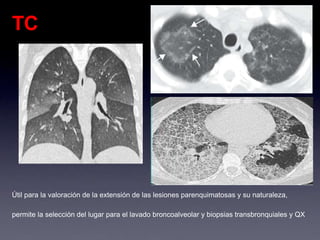

TC

Útil para la valoración de la extensión de las lesiones parenquimatosas y su naturaleza,

permite la selección del lugar para el lavado broncoalveolar y biopsias transbronquiales y QX